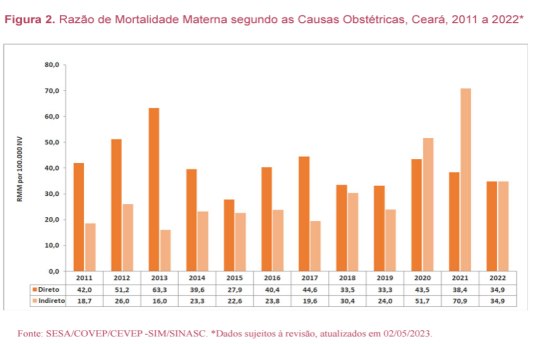

O Boletim Epidemiológico sobre Mortalidade Materna no Ceará, de junho de 2023, apresenta dados com a evolução da RMM de 2011 a 2022, segundo causas obstétricas diretas e indiretas. Com base na figura 2, analise as sentenças que se seguem:

I- A Razão de Mortalidade Materna Específica (RMME) por causas de mortes maternas obstétricas diretas sempre apresentaram valores superiores às indiretas.

II- A relação entre RMM por causas diretas sobre as indiretas caiu de 2,3 em 2011 para 0,5 em 2021.

III- O aumento de proporção de causas indiretas indica uma provável melhoria nas investigações dos óbitos suspeitos.

IV- Em 2021 e 2022 houve uma inversão, as causas indiretas ultrapassaram as diretas, certamente influenciada pela ocorrência da pandemia de covid-19.

V- Em 2022, houve uma redução nas causas indiretas, provavelmente devido às medidas de prevenção e vacinação contra a Covid-19.